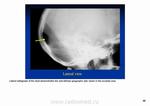

Не похоже?

на 3 рисунок сверху похоже, но только без склеротического ободка.

1. И все равно придумываете. 2. Эта картина похожа на гемангиому (что и показал Валентин Львович). 3 Как бы вам объяснить? Короче, была бы шишка при метастазе таких размеров.

Гемангиома. Типичная локализация в области теменного бугра, гладкий, четкий контур, фестончастые края, намечающаяся звездчатая структура. Все типично. Хрящевых опухолей в костях свода не бывает. Там нет хряща.